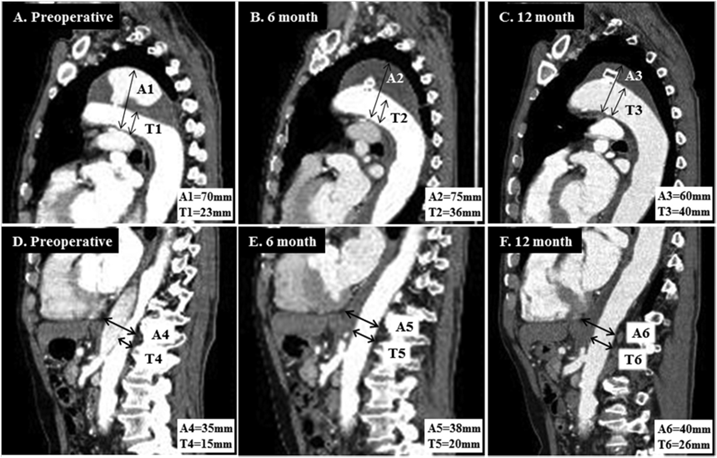

2007~2016年间的14例扩张性慢性主动脉夹层患者(被认为不适合标准治疗)接受了位于主动脉弓(n=6)或降主动脉(n=8)近端破口的腔内血管塞栓塞治疗。其中10例(71%)患者实现了近端破口的栓塞。并在所有10例成功栓塞的患者中,观察到胸主动脉最大直径减小。扩张性慢性主动脉夹层近端夹层破口的腔内栓塞可诱导良好的主动脉重构。对于不适合开放修复或TEVAR的扩张性慢性主动脉夹层患者,采用腔内血管塞栓塞近端破口是一种微创和安全的选择。

病例1为72岁的男子曾因AAA接受治疗,被诊断为70 mm的Ⅲb型主动脉夹层。使用Amplatzer血管塞封闭了5 mm内膜破口,成功修复。患者顺利出院,无并发症,随访CT显示,血管塞无移位,主动脉直径变小。

病例2为75岁女性因Stanford A型主动脉夹层行紧急升主动脉置换手术,残留降主动脉破口。使用AVP Ⅱ顺利栓塞破口,随访影像显示假腔血栓化。

病例3为79岁男性,患者有DeBakey Ⅰ型主动脉夹层。患者不耐受开放手术,使用AVP栓塞近端破口,顺利实现封堵。随访CT显示假腔血栓化。

综上所述,现有应用AVP栓塞主动脉夹层裂口的病例报告表明了该技术的可行性和有效性。该技术操作简便易行,疗效显著,是否常规应用取决于病变本身特点,包括解剖学条件,患者的自身情况、裂口大小等。后期还需要大规模前瞻性研究以改写或增补指南。